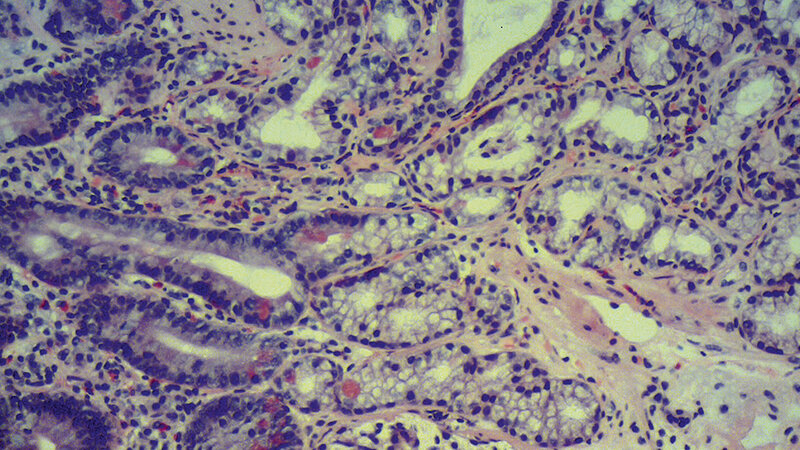

Der Darm ist das größte innere Organ und hat eine entscheidende Aufgabe und Bedeutung für die Gesundheit des Menschen. Es gibt eine Reihe von Erkrankungen, die im Darm entstehen können. Das kolorektale Karzinom ist eine der häufigsten Tumorerkrankungen im Darm. Bis zu 20 % der kolorektalen Adenokarzinome haben eine Mikrosatelliteninstabilität, die mittels der Immunhistochemie bestimmt werden kann und therapeutisch sowie diagnostisch von Bedeutung ist. Bei der Differenzialdiagnose von malignen und benignen Darmerkrankungen spielen die Histopathologie und die Immunhistochemie eine große Rolle.